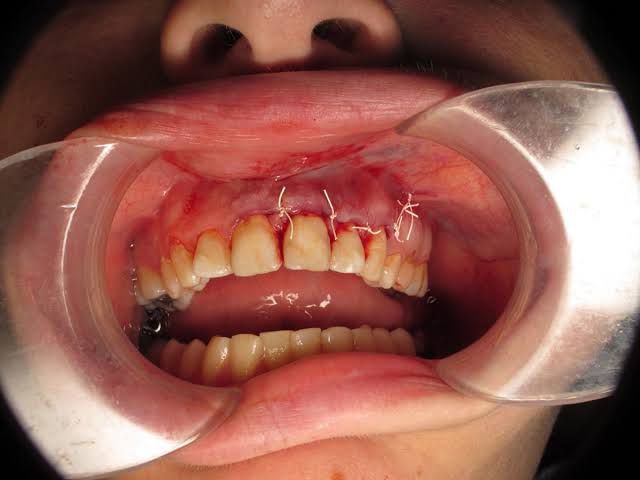

An apicoectomy is a common dental procedure where inflamed gum tissue and the end of the root of your tooth is removed while the top of your tooth is left in place. It's often called a root-end resection because it works on the end (or, tip) of your root called the apex.